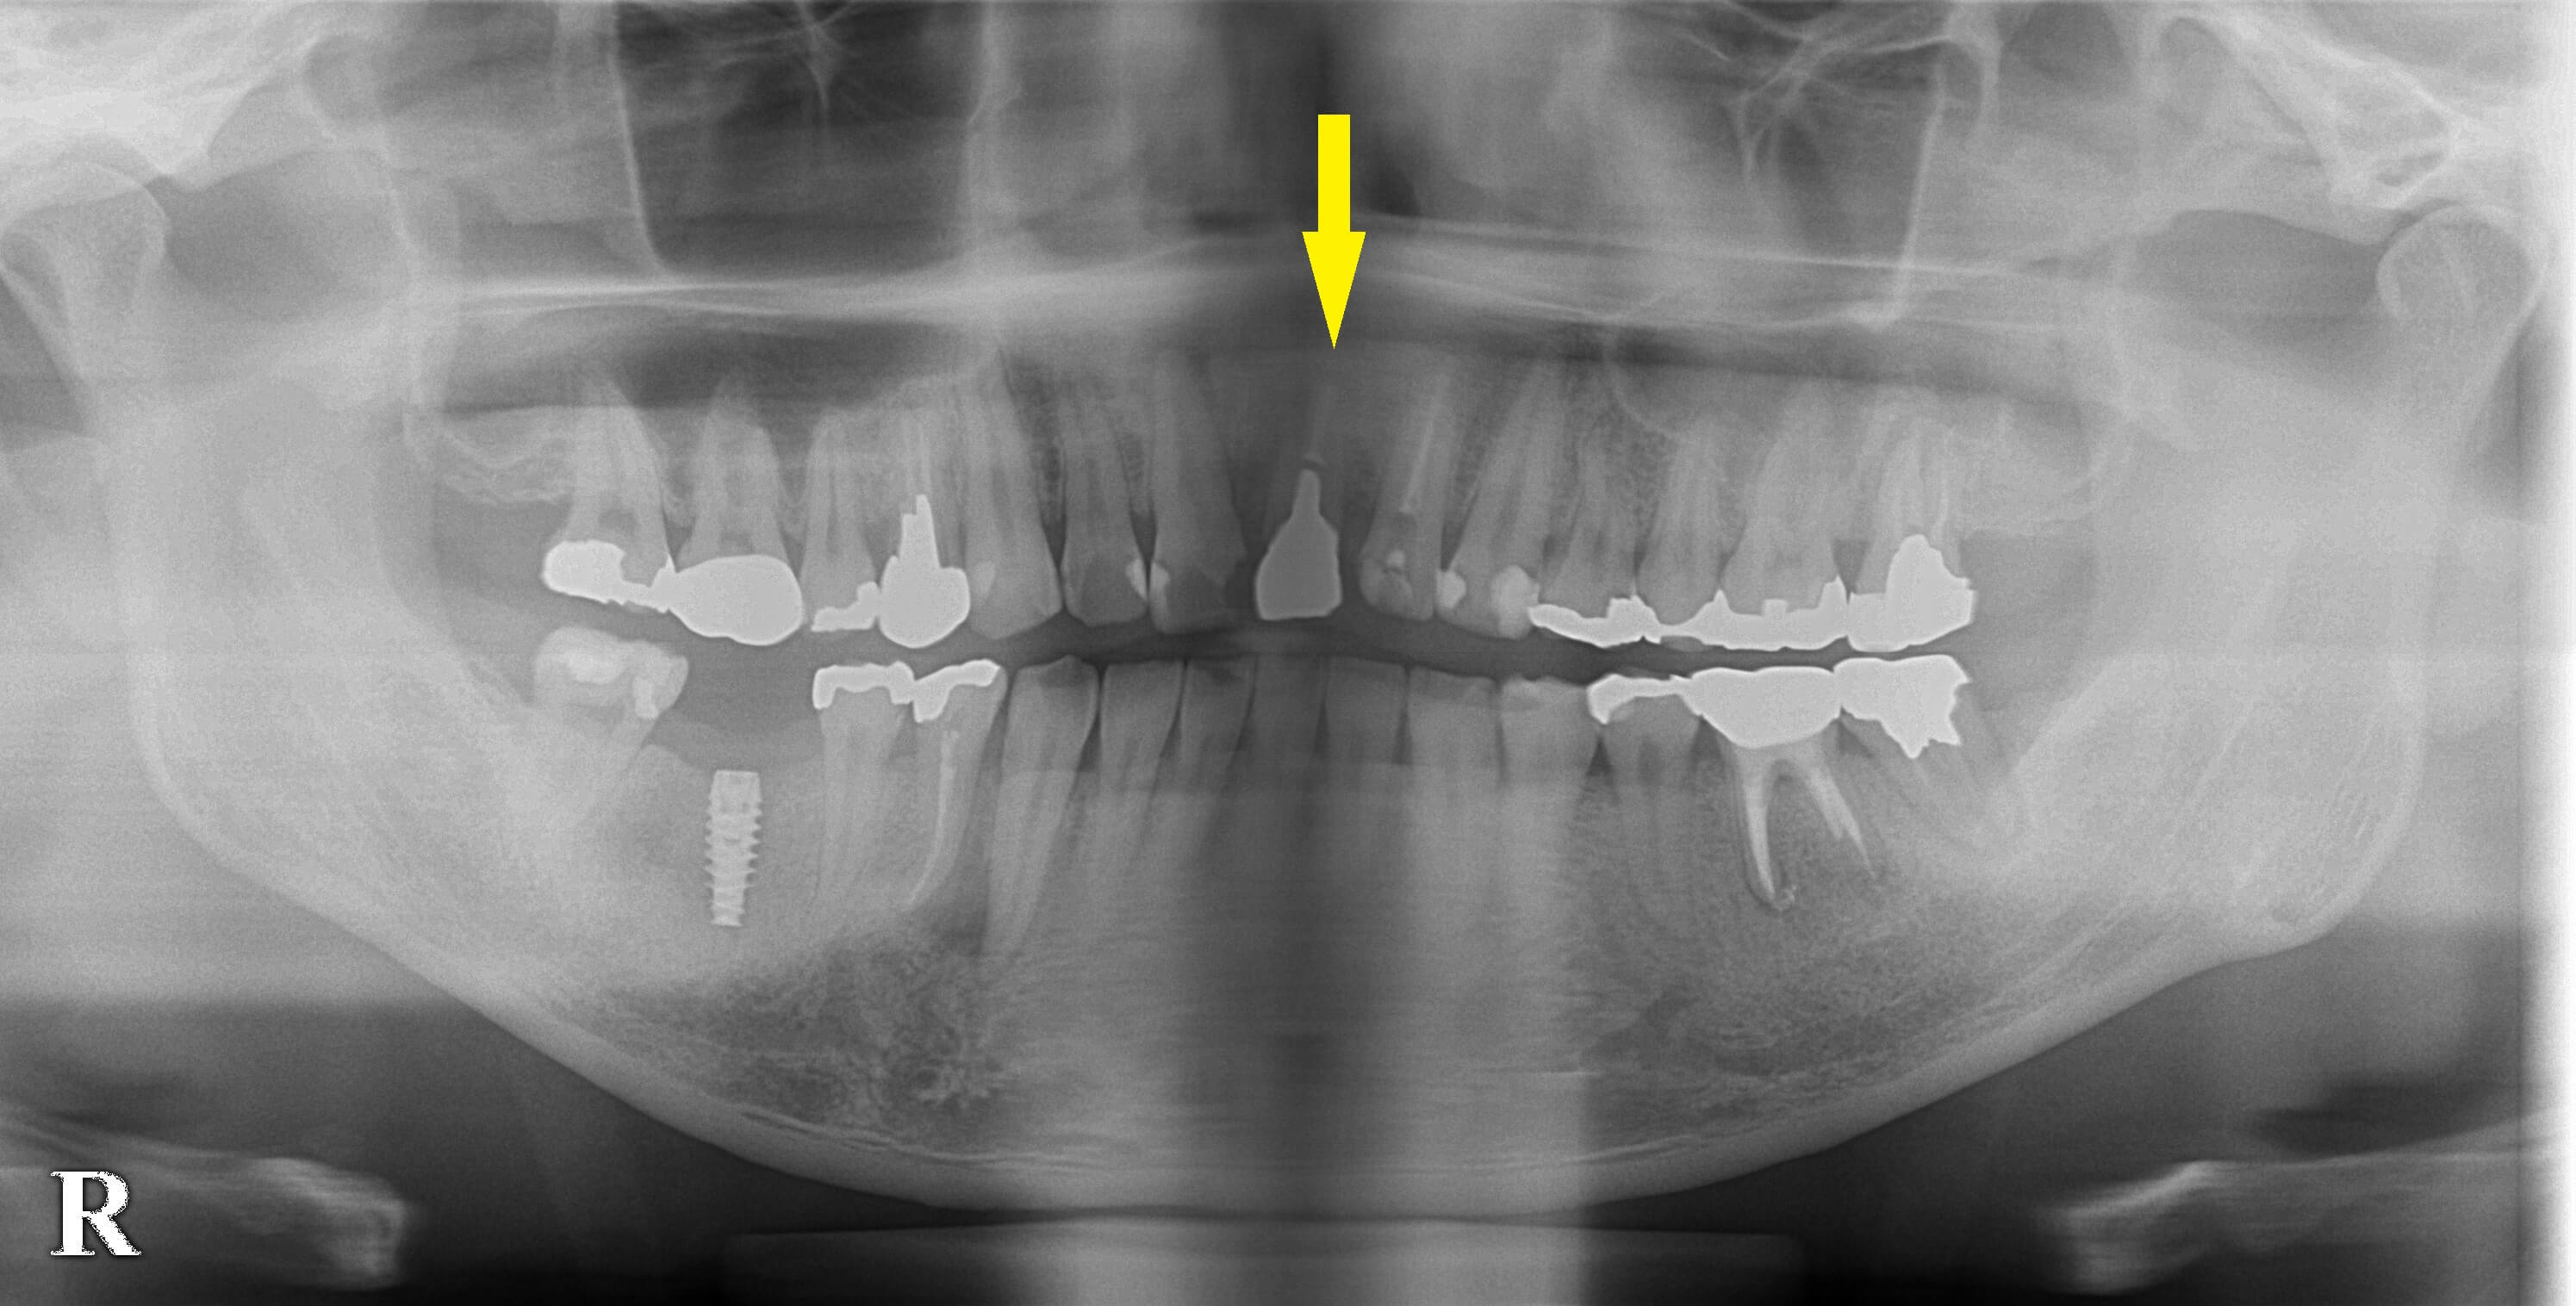

他院で、右下顎大臼歯のインプラント埋入術を受けられて、上部構造セットの予定をされていたそうです。

左上顎前歯がグラグラし始め、診ていただいたところ、

歯根が破折しており、抜歯して、インプラントが必要と言われたそうです。

本日、上顎前歯の、抜歯即時インプラント埋入術を行いました。

下の写真下段左が、手術前のCT、下段右が手術後のCTです。